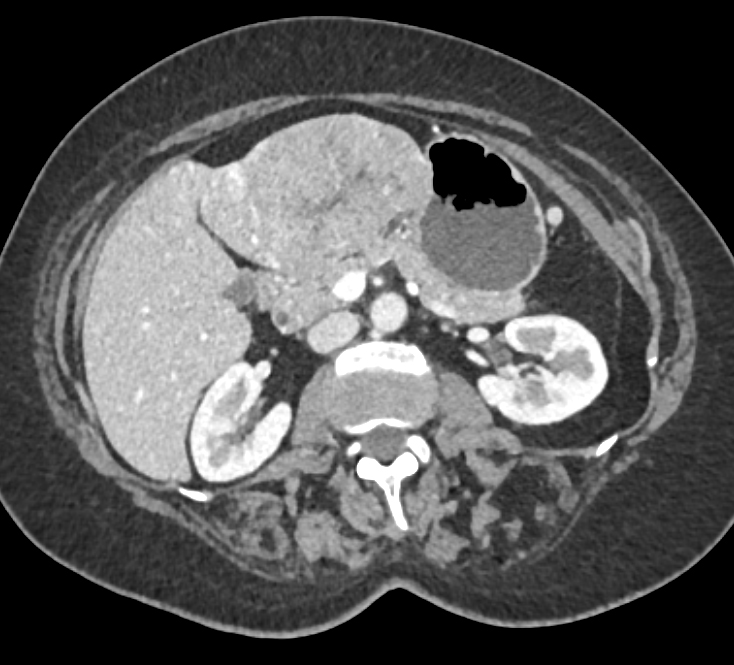

Diagnostic Case Quiz ❯ Anatomical Region Quiz: Liver

The most likely dx in this case is?

hepatic adenoma

focal nodular hyperplasia

hepatoma

hemangioma